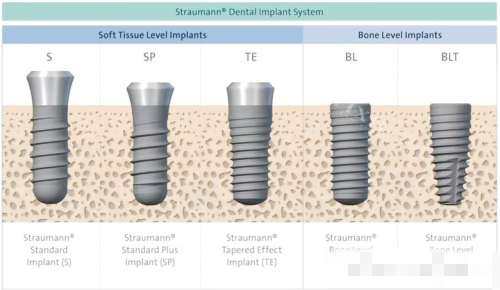

三、不同骨质类型的种植体选择策略

骨质类型 推荐种植体类型 关键技术 适用场景

Ⅰ类骨 自攻型、锥形种植体 控温钻孔、减少攻丝 前牙区单颗缺失

Ⅱ类骨 常规圆柱形种植体 All-on-4即刻负重 全口/半口修复

Ⅲ类骨 双螺纹、颈部外展种植体 骨挤压、双层皮质骨固定 下颌后牙区骨量不足

Ⅳ类骨 半自攻、光滑颈圈种植体 上颌窦提升、骨挤压 上颌后牙区骨密度低